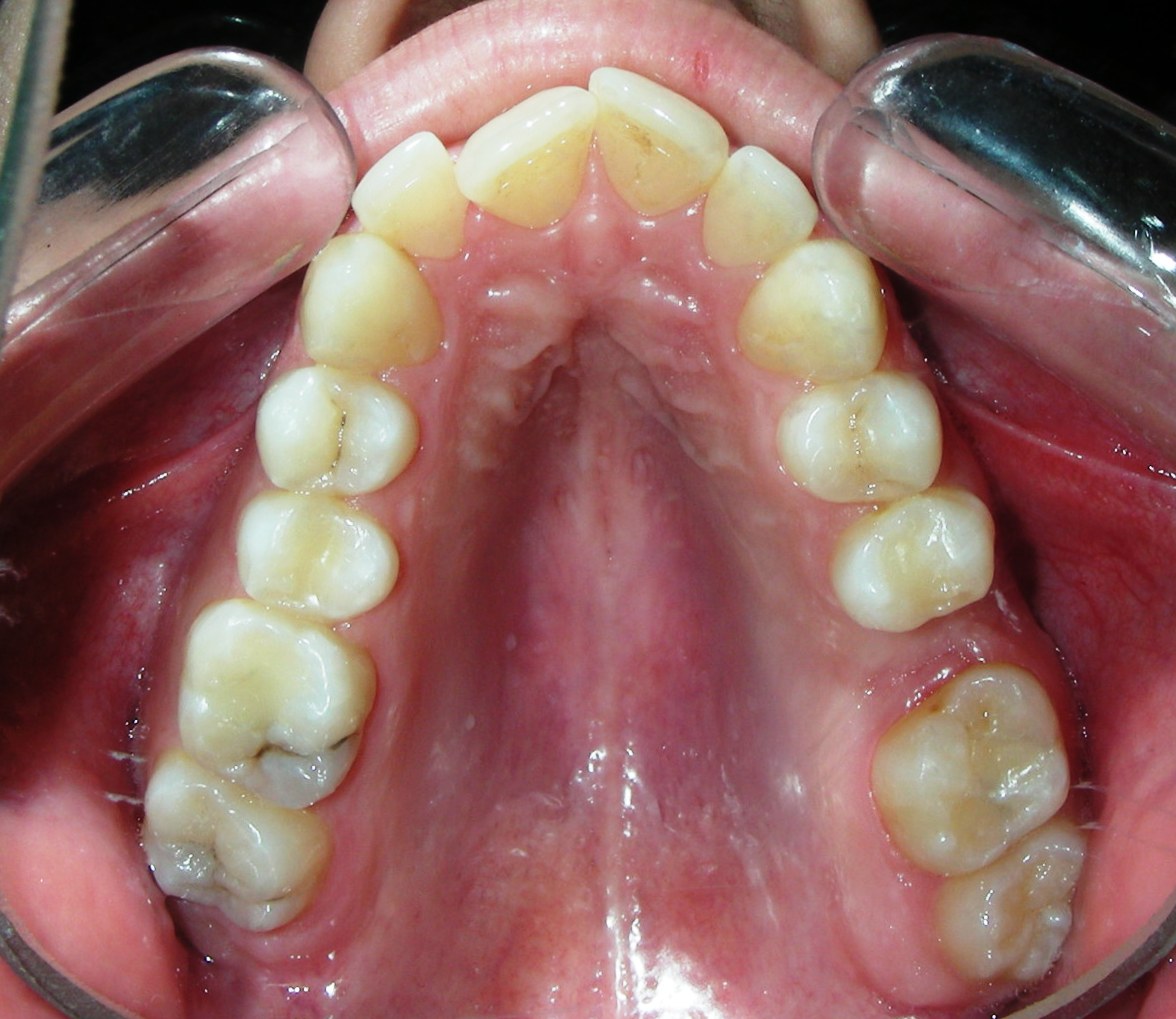

Intraoral Examination:

Absent #16, #36 and #46 , No Angle molar relationship . Projection of canines axes in class II relationship . Anterior open bite: Over Bite – 8 mm). Bilateral posterior crossbite: Involvement of upper posterior sectors with inverted buccal-lingual relationship. Moderate Crowding at the level of the upper and lower incisors. Acceptable Oral Hygiene with no periodontal issues